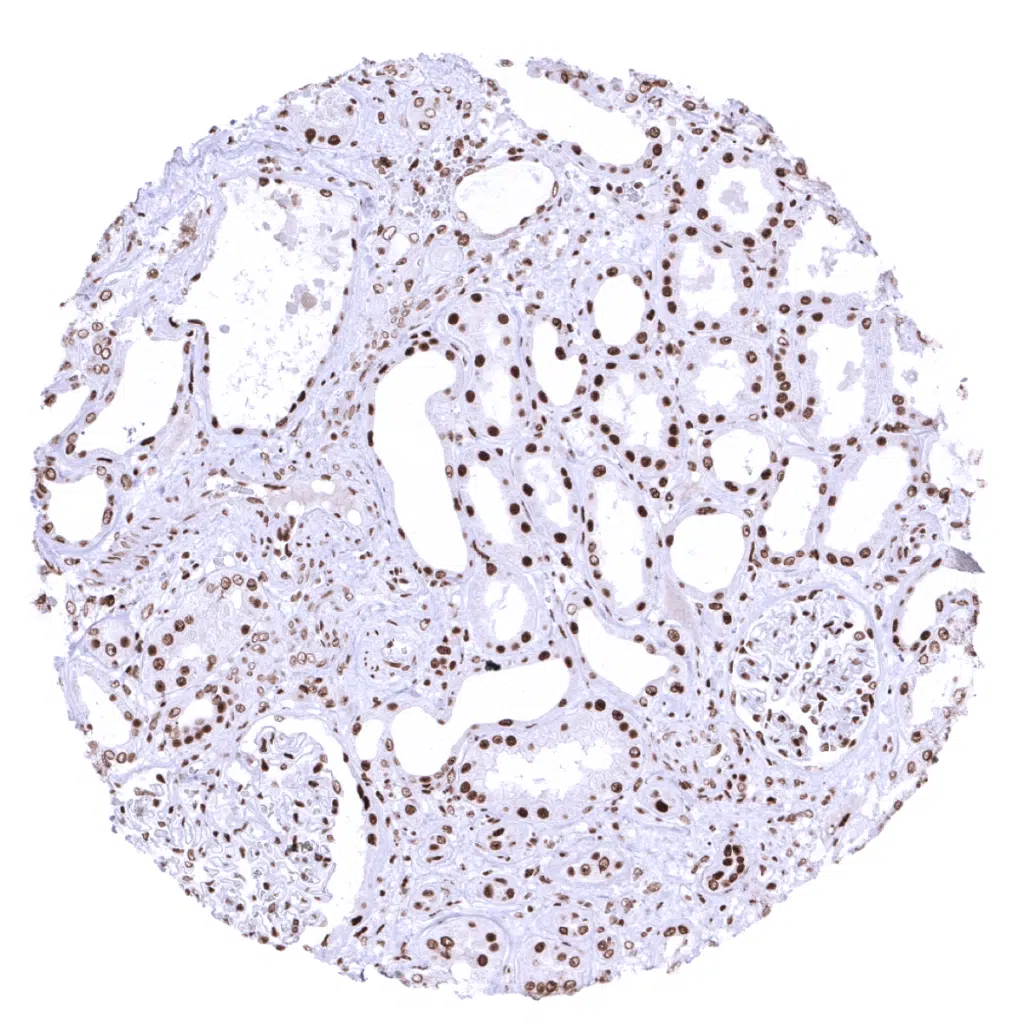

Kidney, cortex